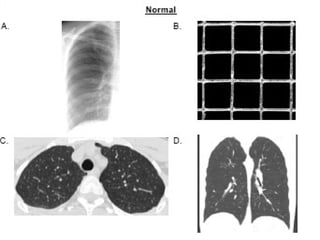

Radiography

Patterns of Interstitial Lung DiseasePatterns of Interstitial Lung Disease